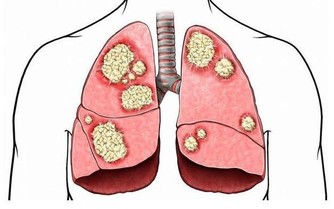

***5、修復免疫功能***

據相關的研究發現,午睡能有效的刺激體內淋巴細胞,增強免疫細胞的活性,使得免疫系統可以在這期間得到某種修復,從而提高身體的免疫,抵抗病毒的入侵,維持身體的健康。